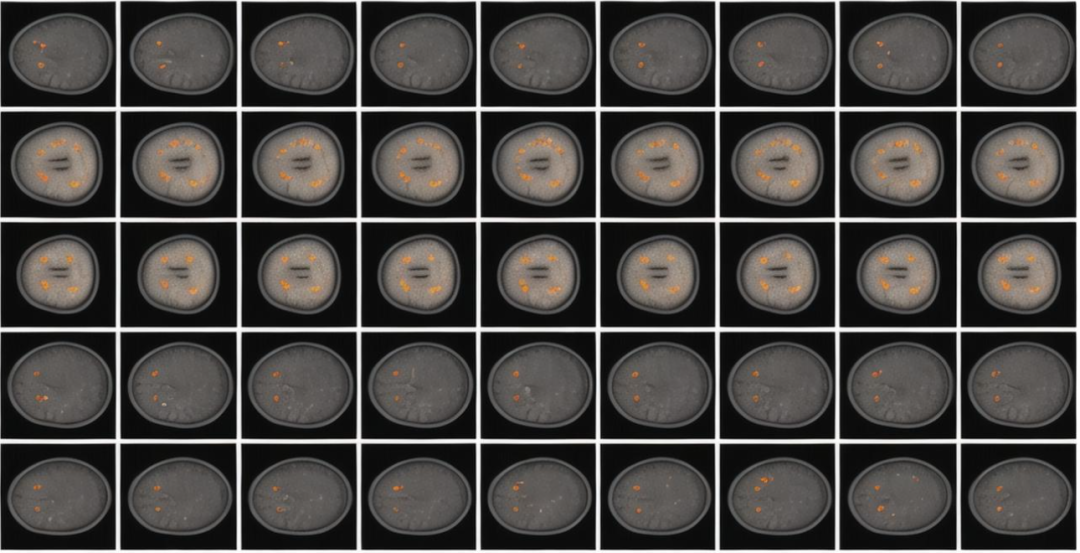

在我们的实验中,我们首先分析了在域转移背景下的公平性,具体关注于杯盘分割任务。杯盘分割是指在眼底图像中精确描绘视杯和视盘的过程,这对于计算杯盘比(CDR)至关重要,是评估青光眼进展和风险的关键参数。

这一任务在医学影像领域尤为重要,尤其是在诊断和管理青光眼等眼科疾病时。由于视杯是视盘的一个重要子区域,我们将分割任务重新定义为视杯和边缘(视杯和视盘边缘之间的组织区域)分割,以避免因视杯和视盘之间的大面积重叠而导致的表现失真。

我们研究了在三种不同的人口统计特征(性别、种族和族裔)下的公平性表现,涉及两个不同的领域:从光学相干断层扫描(OCT)中获取的 En face 眼底图像和扫描激光眼底图像(SLO)。

在随后的实验中,我们选择 En face 眼底图像作为源域,SLO 眼底图像作为目标域。其原因在于,与 SLO 眼底图像相比,En face 眼底图像在专科眼科护理环境中更为常见,因此数据的可用性显著更高。

因此,我们选择将 En face 眼底图像作为源域,将 SLO 眼底图像作为目标域。对于分类任务,我们使用这两个域的眼底图像作为源域和目标域,分类为正常和青光眼两类。